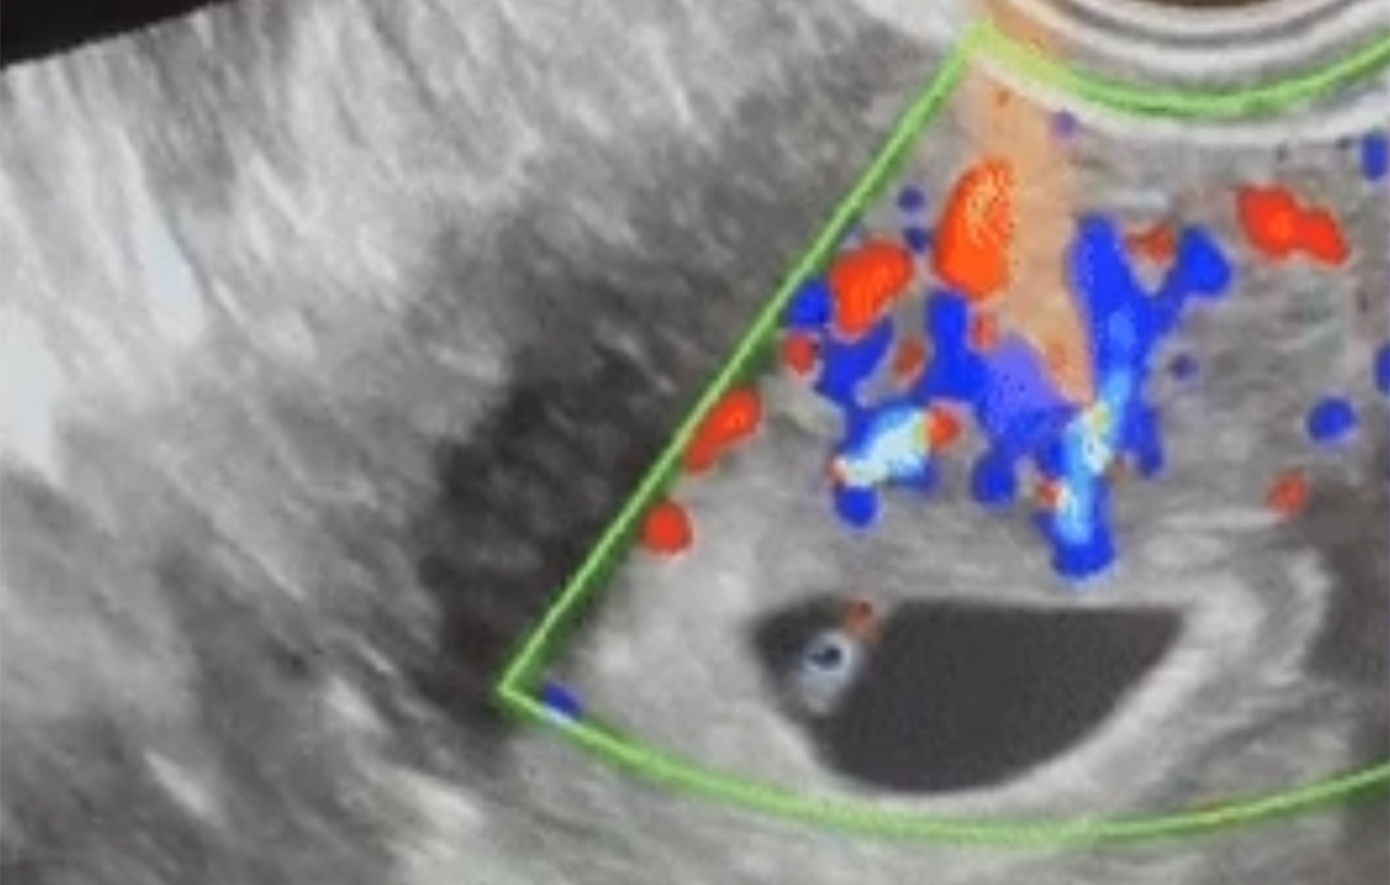

Στην εικόνα από το «Business Insider» φαίνεται το υπερηχογράφημα του εμβρύου που δημιουργήθηκε με την πρώτη απομακρυσμένη ICSI της Conceivable.